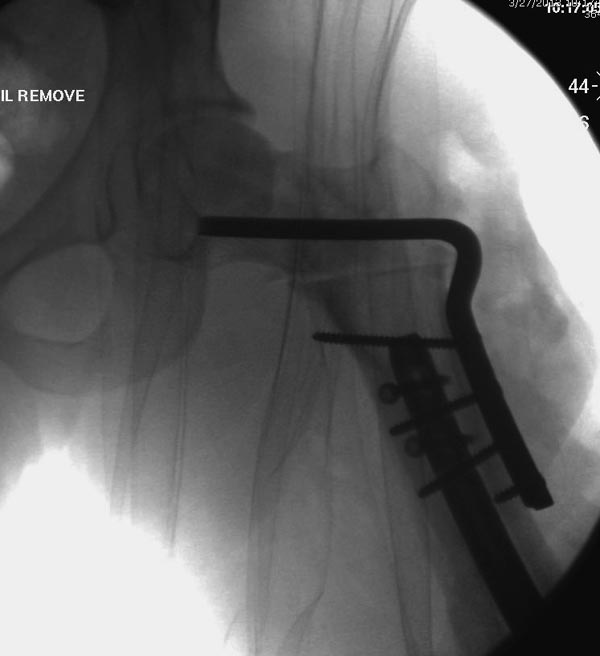

несращения! По истечению 4 месяцев появились признаки варусной

деформации. На СТ срезах несращение шейки и бедра. Риминг, замена на

более толстый гвоздь и вальгусная остеотомия.